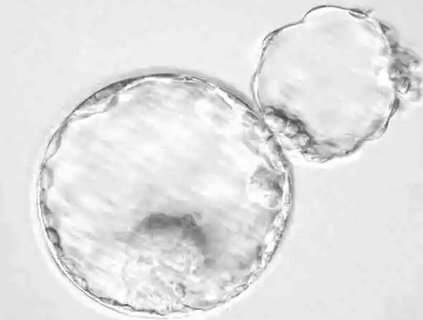

技術(shù)定義:輔助孵化是在胚胎的透明帶進(jìn)行微小的切口或削弱,以促進(jìn)胚胎孵化。

透明帶作用:透明帶過(guò)厚或其他因素可能阻礙胚胎正常孵化。